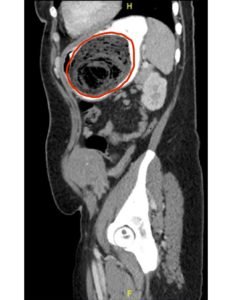

Computed tomography (CT) of the abdomen and pelvis with oral and intravenous contrast was ordered to evaluate her symptoms. The CT showed three large collections of ingested material seen as hypodense material with circular rings surrounded by the hyperdense oral contrast (see red outlines). These findings are consistent with bezoars, the largest of which measured 11.5 x 7.8 cm. There was also thickening of the gastric wall (see blue outline), most notably at the pylorus, consistent with partial obstruction.